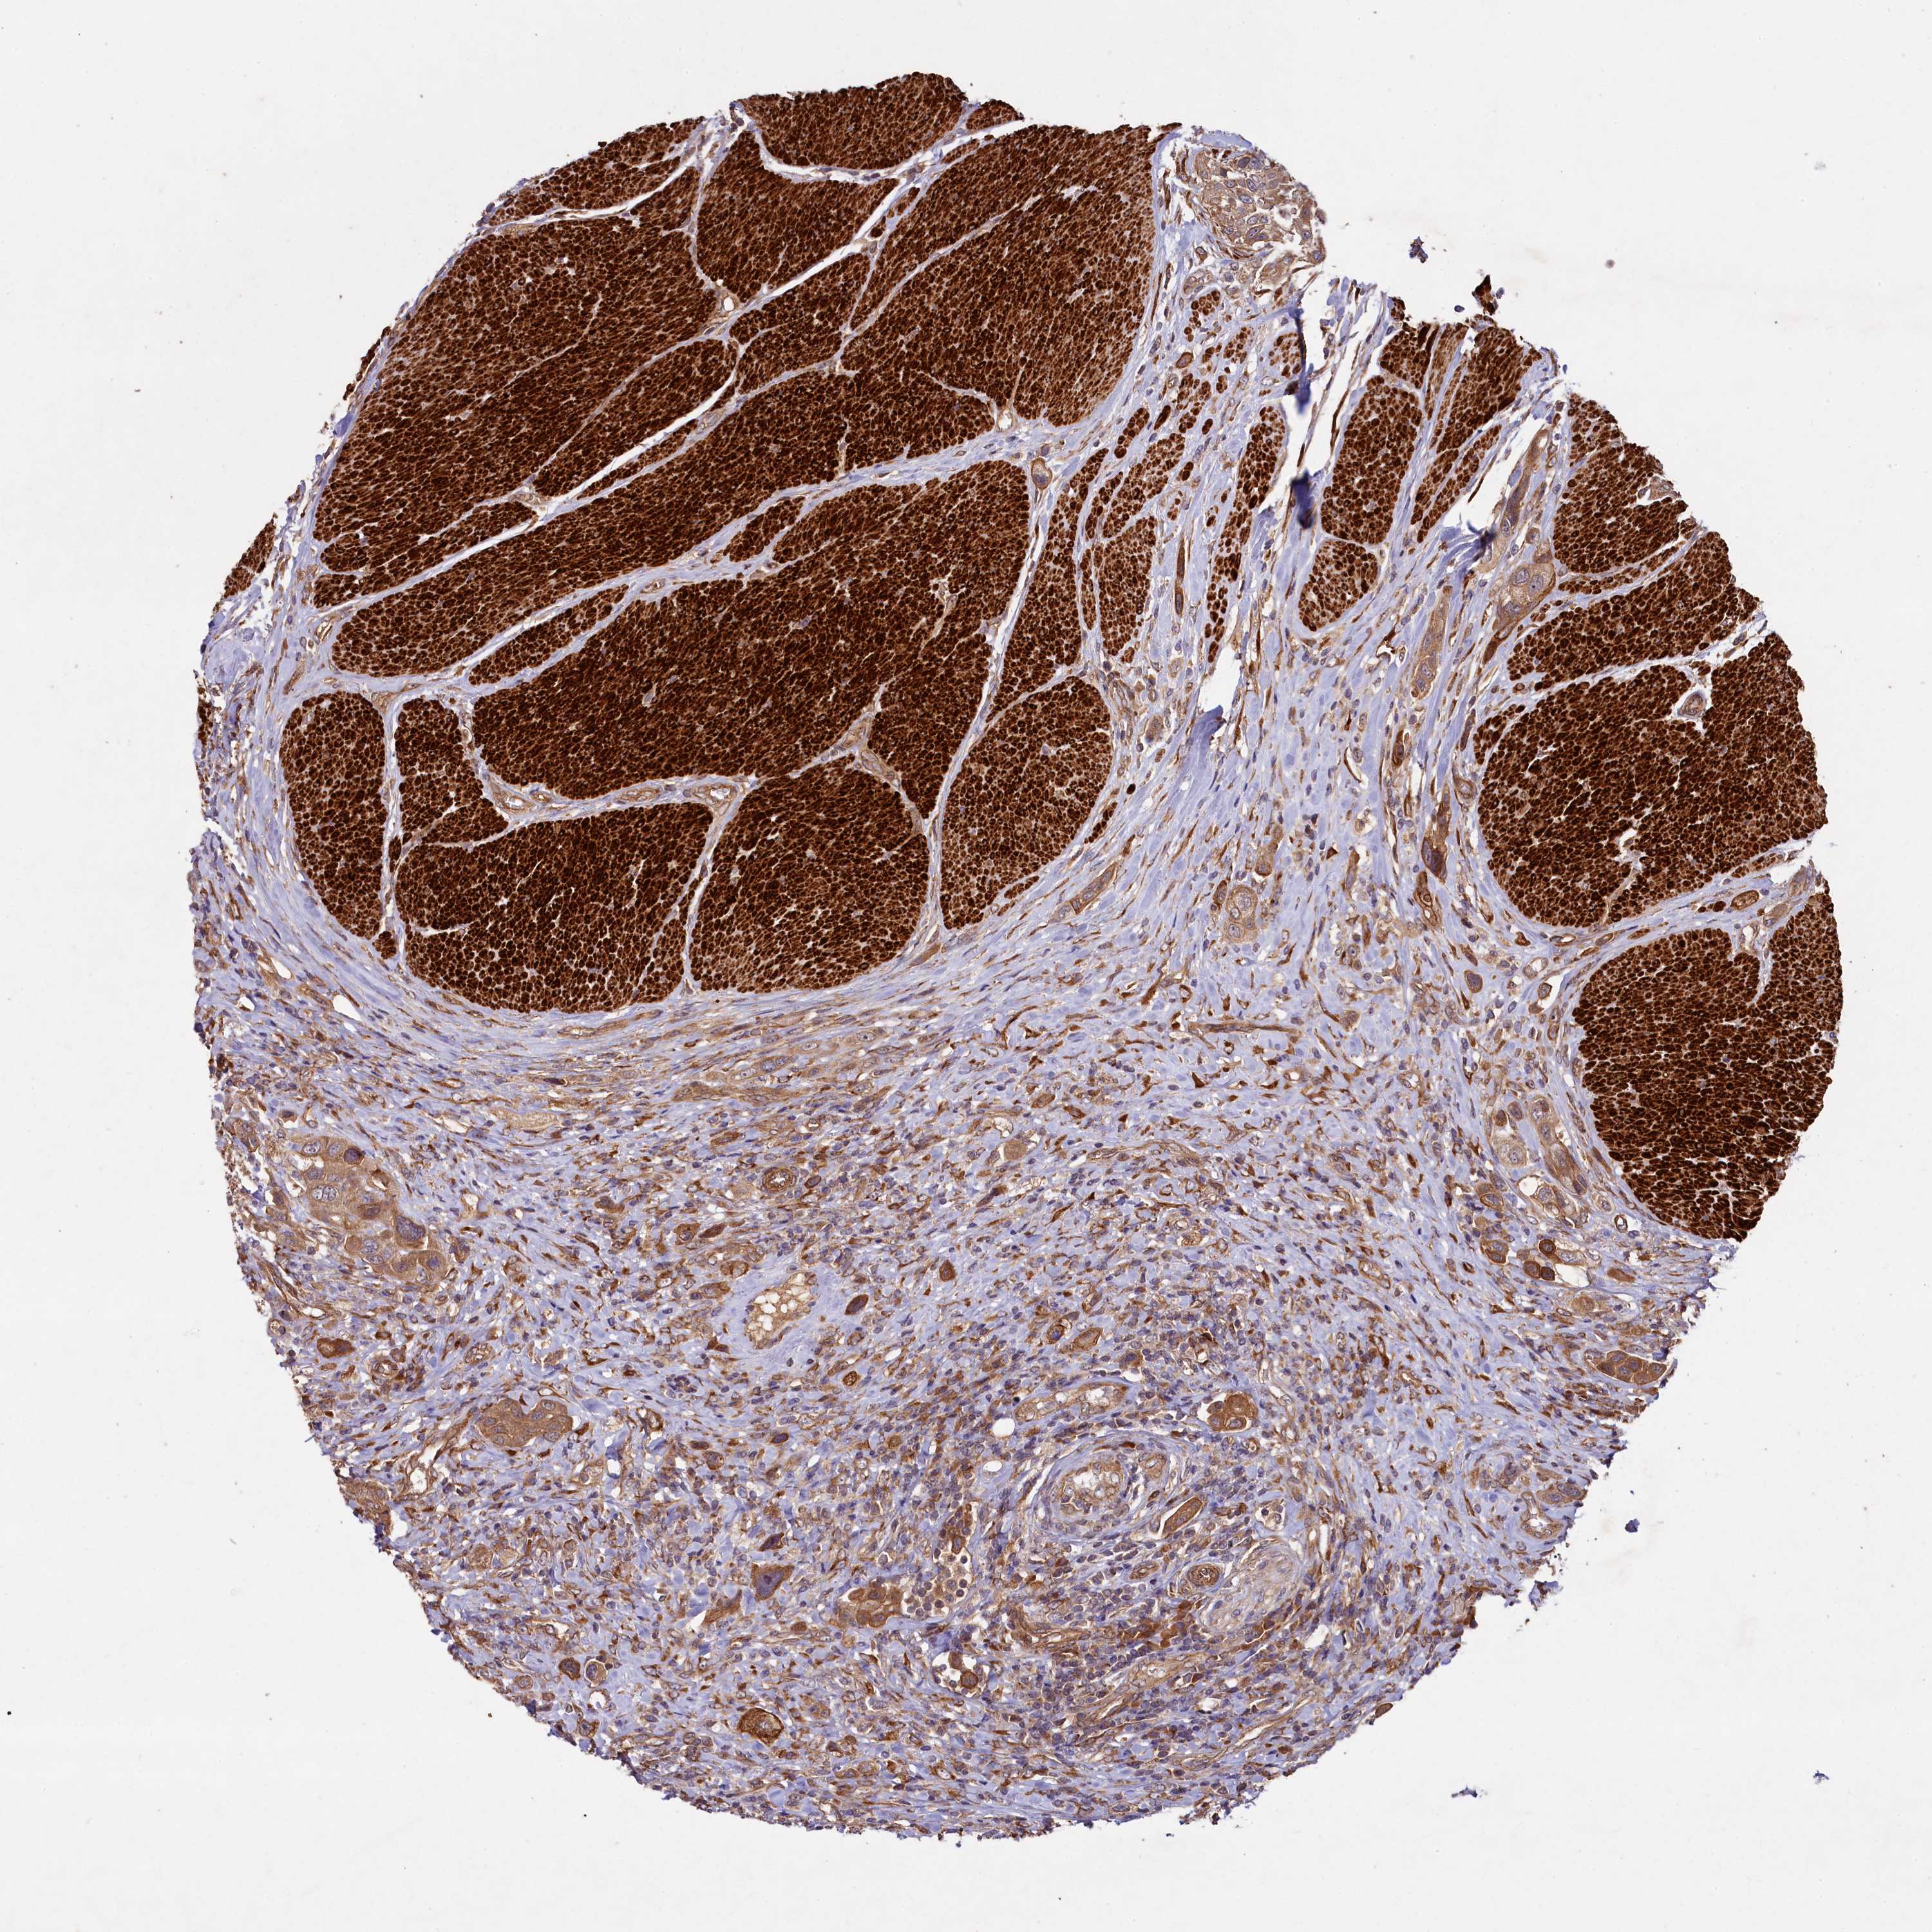

UROTHELIAL CANCER - Protein expressioni

A mouse-over function shows sample information and annotation data. Click on an image to view it in a full screen mode. Samples can be filtered based on level of antibody staining by selecting one or several of the following categories: high, medium, low and not detected. The assay and annotation is described here.

Note that samples used for immunohistochemistry by the Human Protein Atlas do not correspond to samples in the TCGA dataset.

Antibody stainingi

Antibody staining in the annotated cell types in the current human tissue is reported as not detected, low, medium, or high, based on conventional immunohistochemistry profiling in selected tissues. This score is based on the combination of the staining intensity and fraction of stained cells.

Each image is clickable and will lead to virtual microscopy that enables deeper exploration of all samples and also displays staining intensity scores, fraction scores and subcellular localization as well as patient and tissue information for each sample.

Antibody HPA040598

Antibody HPA040958

Urothelial carcinoma, High grade

Urothelial carcinoma, Low grade